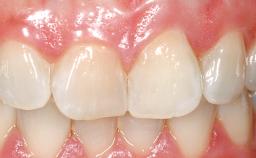

Immediate Placement of an Implant in a Maxillary Left Central Incisor Site

A 33-year-old female patient presented with an upper left central incisor that required extraction after a failed endodontic therapy. The tooth had been traumatized when the patient was a teenager and had undergone several endodontic treatments, including two apicectomy procedures. The patient was in good health and did not smoke. Clinical examination showed that the patient had a high lip line. In full smile, the gingival margins of the upper teeth were visible to the first molars. The gingival margins of central incisors 11 and 21 were only just showing. Examination of tooth 21 confirmed that the tooth was mobile and had hypererupted by 1 mm.

Lip Line No exposure of papillae Exposure of papillae Full exposure of mucosa margin

Periodontal Phenotype Low-scalloped, thick Medium-scalloped, medium-thick High-scalloped, thin